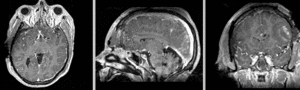

Registration Results

unregistered exam 1 & 2

Exam 2 aligned to Exam 1 (affine only)

Exam 2 aligned to Exam 1 (affine+BSpline)

BSpline deformation only of Exam 2